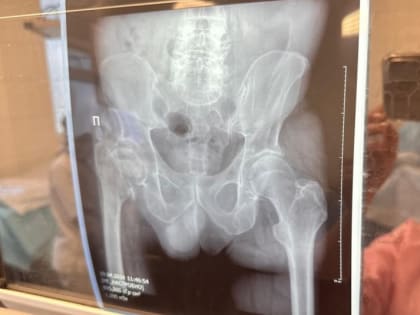

В Хабаровском крае растет число операций по эндопротезированию суставов

Высокотехнологичную помощь пациентам оказывают по полису ОМС Краевая клиническая больница имени профессора Владимирцева увеличивает количество операций по эндопротезированию тазобедренных и коленных суставов,